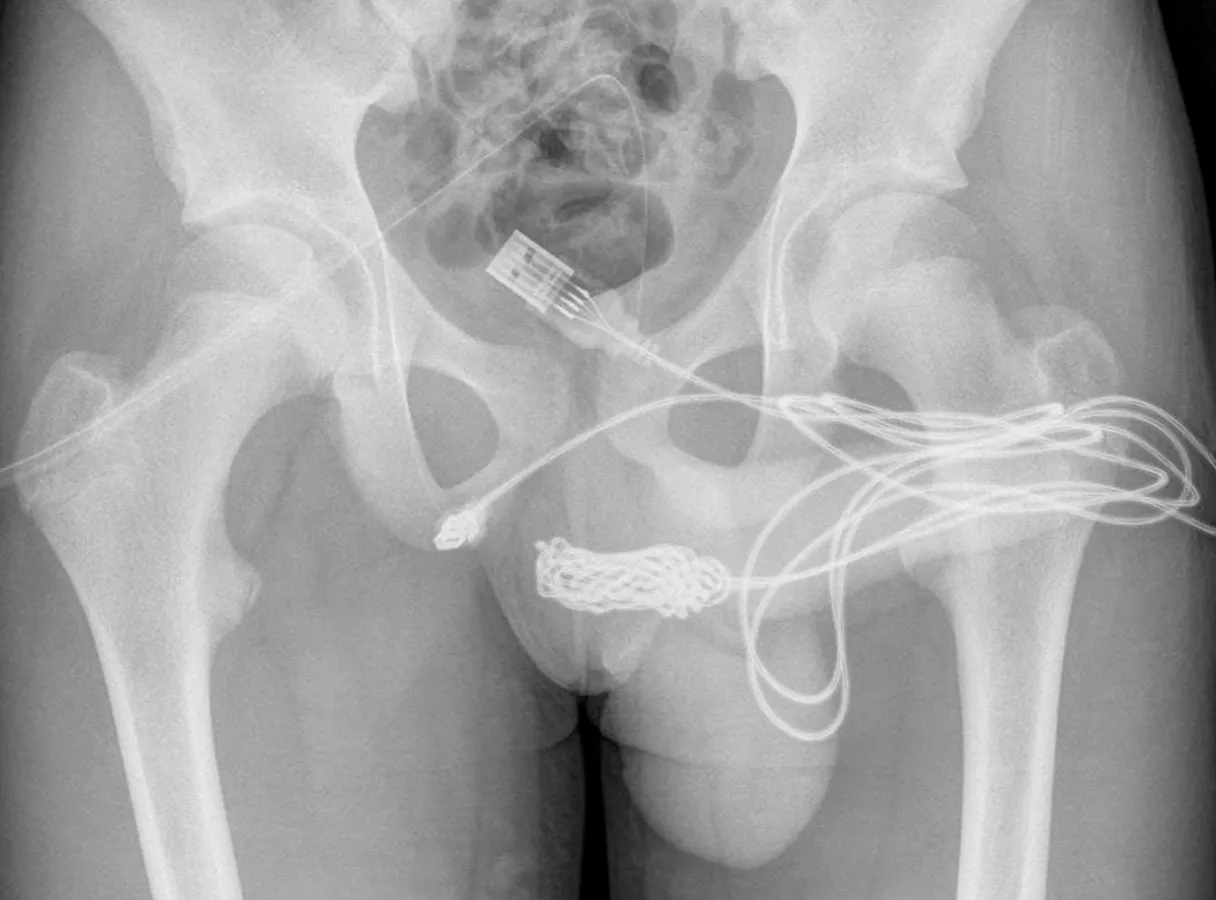

El curioso experimento no tuvo éxito: una vez que comenzó a orinar sangre, sus padres lo llevaron al hospital.Al examinar al joven, de 15 años, los médicos del University College Hospital de Londres vieron que el cable había quedado en su escroto, como si fuera un catéter electrónico. La radiografía reveló que tenía un verdadero nudo dentro de sus genitales.

El propio adolescente, avergonzado, contó a los doctores que se había insertado el cable en la uretra para medir la longitud de su pene «por curiosidad sexual» y había intentado sacarlo por sí mismo.

Para extraer el nudo, los médicos tuvieron que hacer una incisión entre el pene y el ano del paciente.